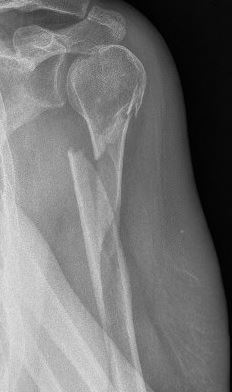

Wanneer het begin van het bovenarmsbot breekt, dan komt dit meestal door een val op de schouder. De klachten kenmerken zich dan door veel pijn in de schouder met een onmogelijkheid de bovenarm of schouder te bewegen. Een bloeduitstorting is vaak pas na enkele dagen zichtbaar. Een Röntgenfoto kan de aanwezigheid en het beloop van de breuk aantonen.

Het bovenarmsbot (de ‘humerus’) is een lange pijpbeen van de schouder tot aan de elleboog. Ter hoogte van de schouder heeft het bovenarmsbot een bolvormige kop, waarmee de bovenarm een gewricht vormt met het komvormige schouderblad. Dit gewricht vormt het schouder gewricht. Een breuk in dit gebied kan net door of onder de kop van het bovenarmsbot lopen en dus door het schoudergewricht of er net onder lopen. Onder de kop begint de schacht van het bovenarmsbot dat doorloopt tot aan de elleboog.